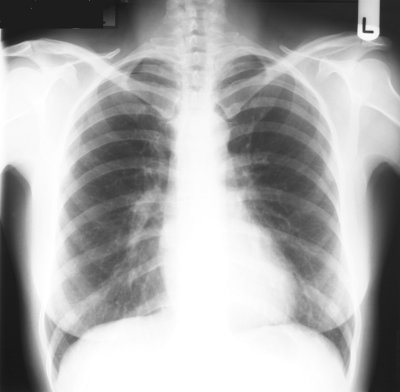

YIKES! To be a mom with no control of what's going on in a different city waiting to meet her son at the emergency room is an absolute nightmare! I also felt terrible for my poor mom who was totally freaked out and worried as well. Once we got to Cooks Childrens they immediately took his vitals and gave him some more meds to help bring down the fever. Within minutes he became much more responsive and actually sat up and started to play with his Woody and Jessie dolls. PTL!! So after a 4.5 hour stay in the hospital for observation and after some of this:

and this:

They determined that there really wasn't anything they could do for him that we couldn't do at home so we were discharged and just every 3 hours have to dose him with fever meds. He's been much better today and hasn't had any super high temps but still stays around 102.0. He's never wanted his Mommy so much in his life so I am loving the cuddle time :)